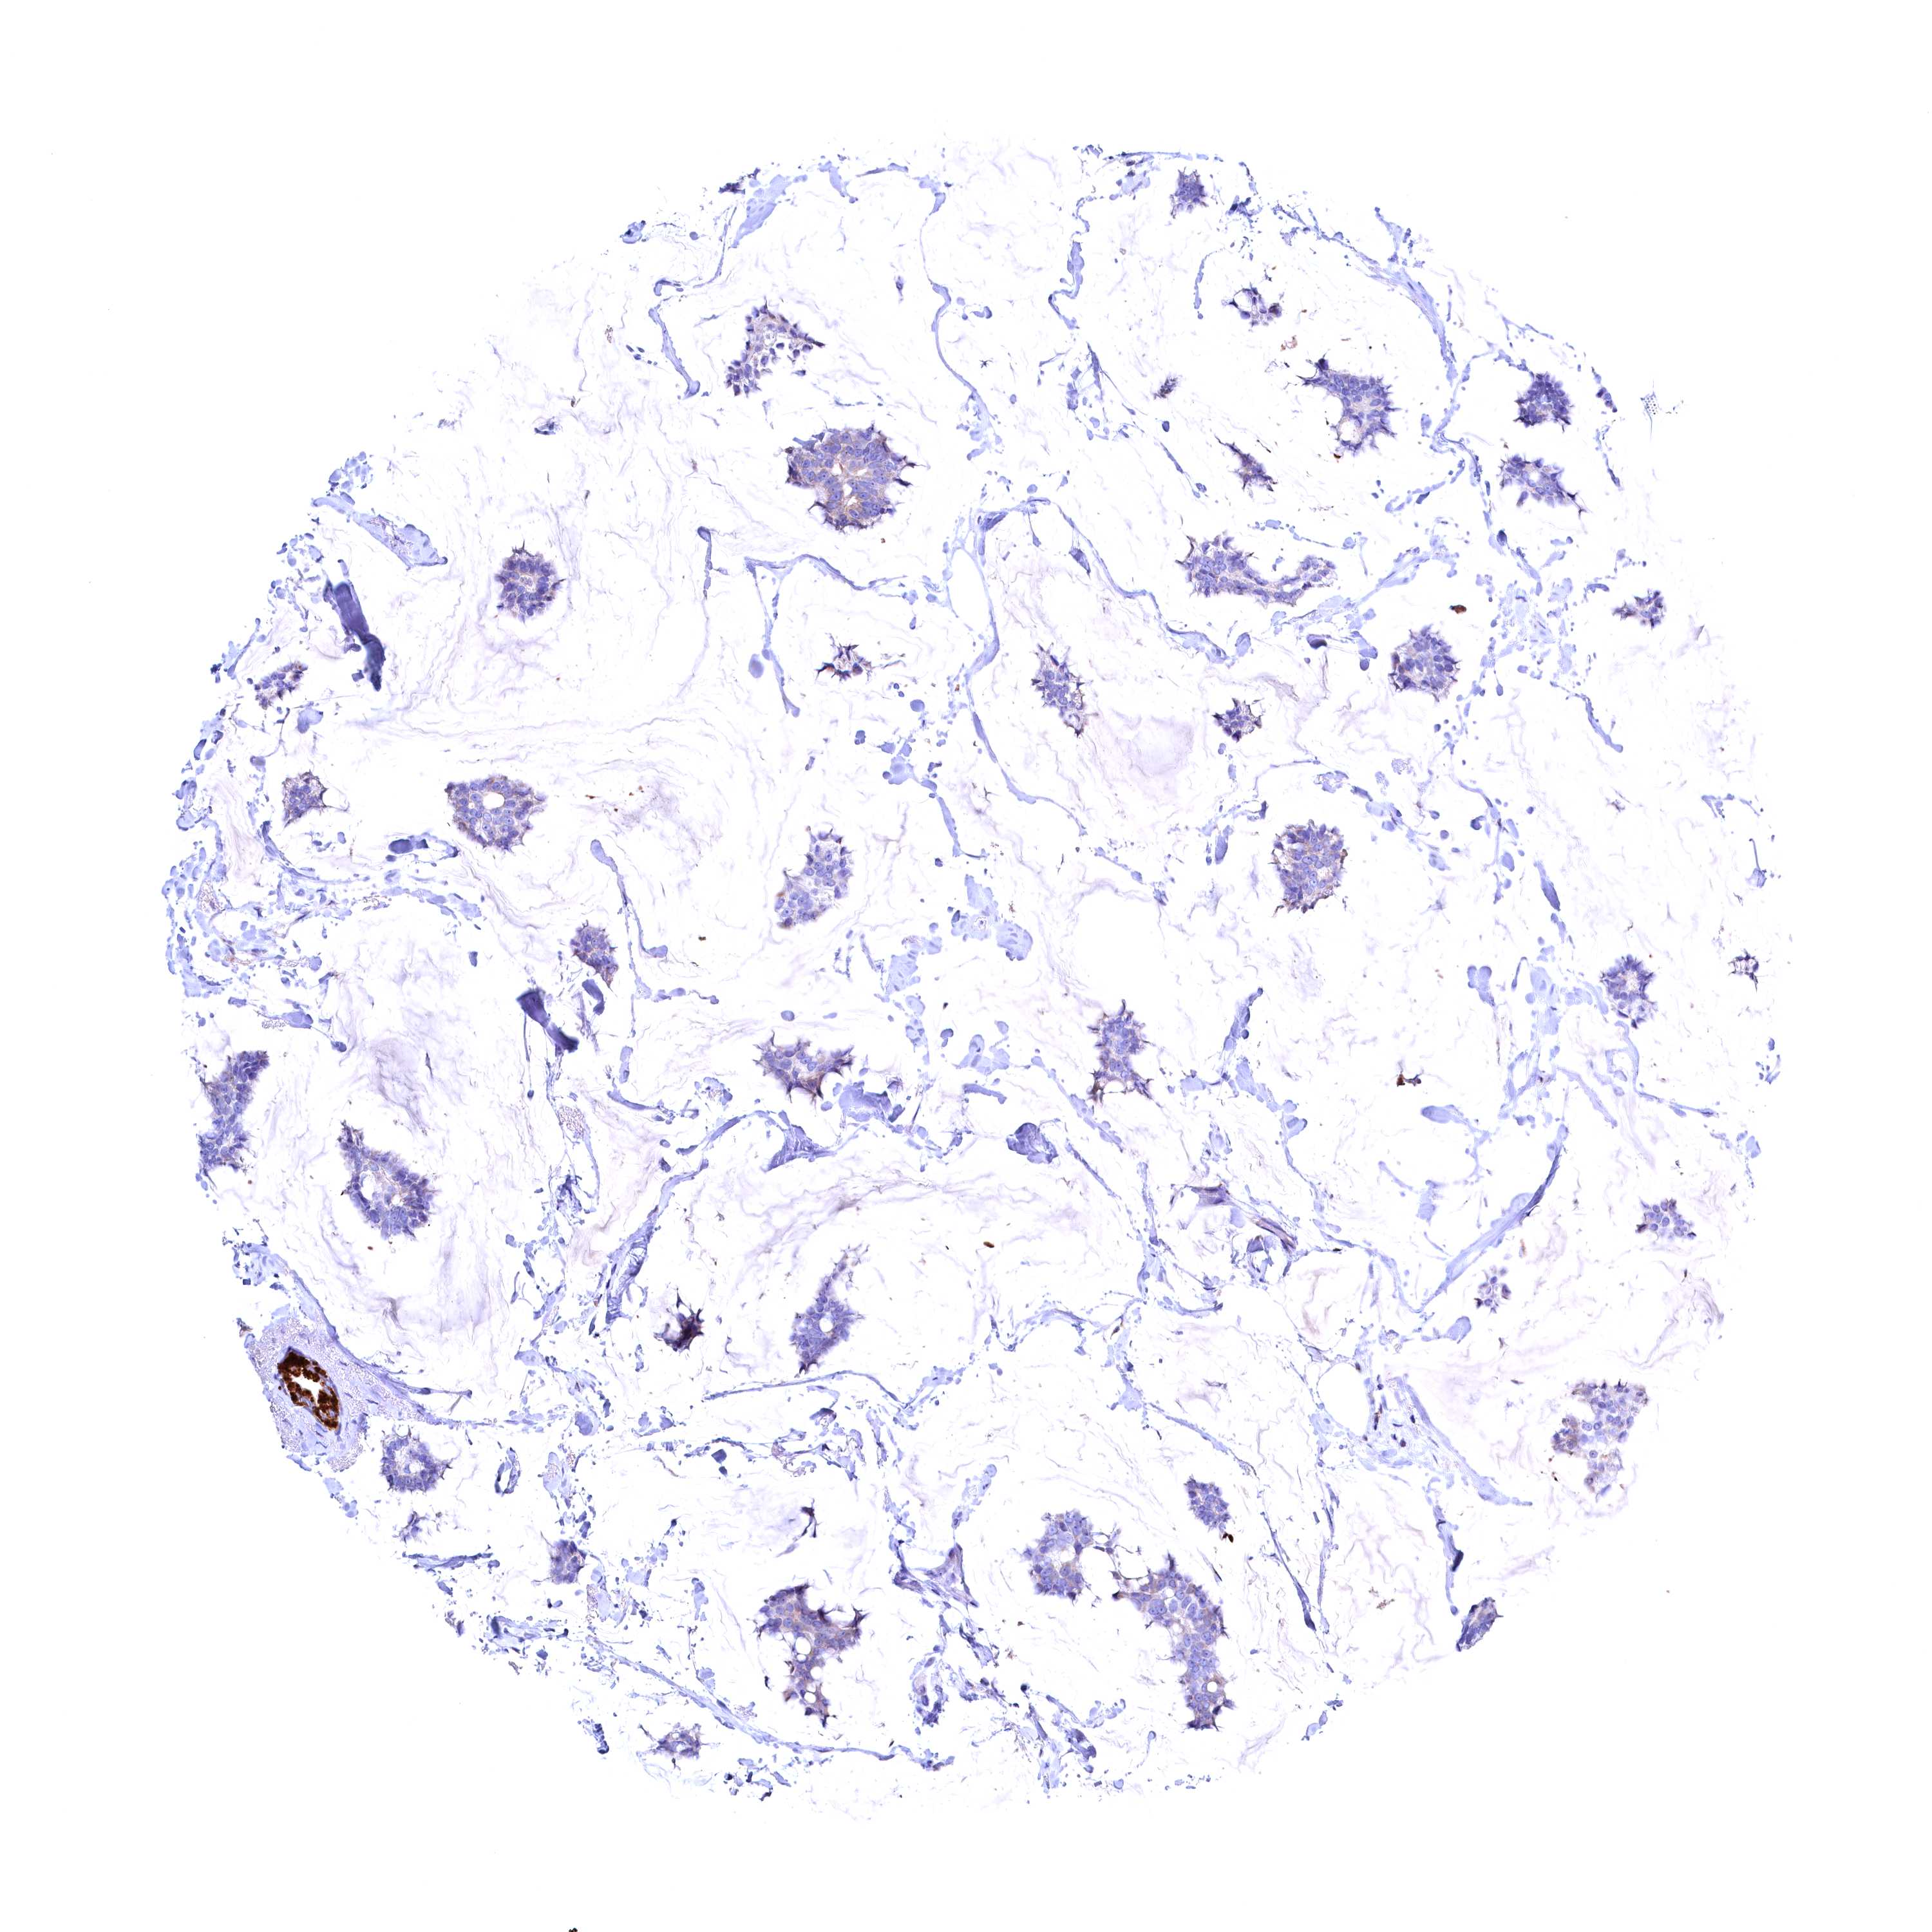

CANCER BREAST CANCER Show tissue menu

BRCA TCGA BRCA VALIDATION PROTEIN EXPRESSION